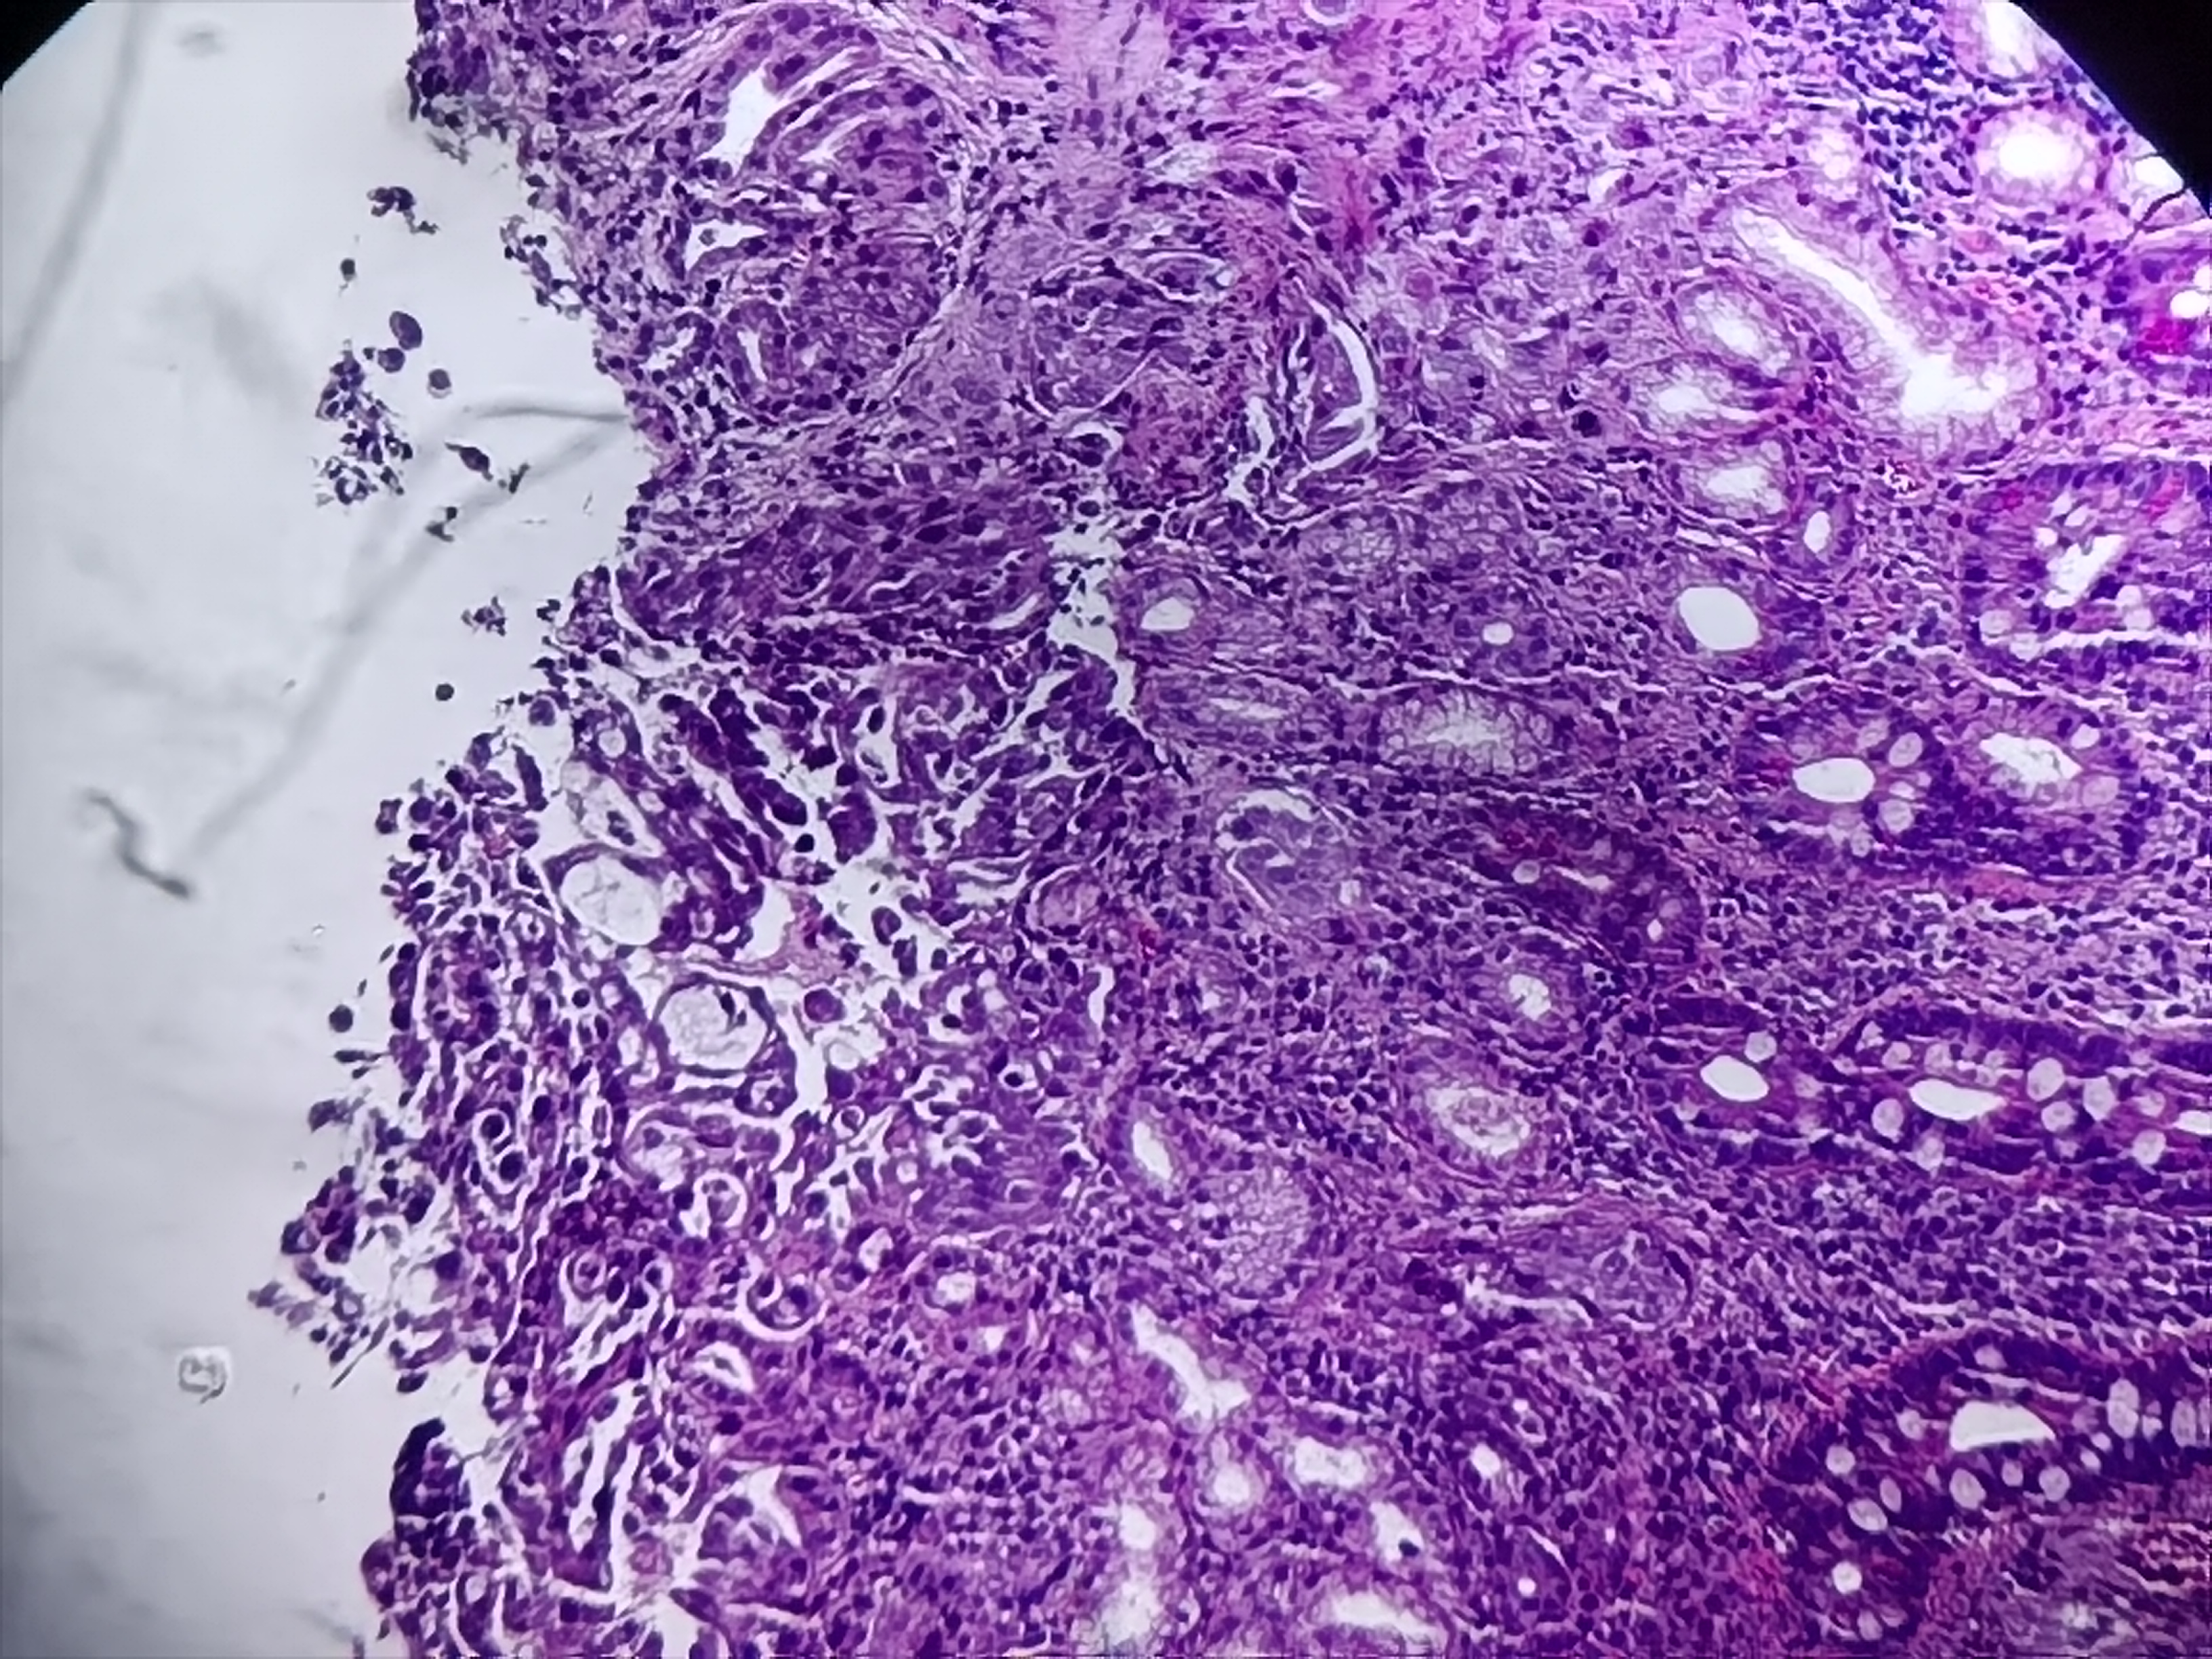

十二指肠球部活检

十二指肠球部可见一大小约0.5*0.6cm隆起性病变

标本名称

十二指肠球部粘膜活检

大体所见

灰白灰红组织1块

异位胰腺组织。